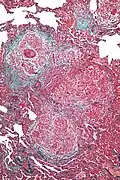

| High magnification photomicrograph of a lung biopsy taken showing chronic hypersensitivity pneumonitis (H&E), showing mild thickening of the walls of the small air sacs by invasion of white blood cells. A multinucleated giant cell, seen within the walls of the air sacs to the right of the picture halfway down, is an important clue to the correct diagnosis. | |

Lung biopsy

Lung biopsies can be diagnostic in cases of chronic hypersensitivity pneumonitis, or may help to suggest the diagnosis and trigger or intensify the search for an allergen. The main feature of chronic hypersensitivity pneumonitis on lung biopsies is expansion of the interstitium by lymphocytes accompanied by an occasional multinucleated giant cell or loose granuloma.[7][22]

When fibrosis develops in chronic hypersensitivity pneumonitis, the differential diagnosis in lung biopsies includes the idiopathic interstitial pneumonias.[23] This group of diseases includes usual interstitial pneumonia, non-specific interstitial pneumonia and cryptogenic organizing pneumonia, among others.[7][22]

The prognosis of some idiopathic interstitial pneumonias, e.g. idiopathic usual interstitial pneumonia (i.e. idiopathic pulmonary fibrosis), are very poor and the treatments of little help. This contrasts the prognosis (and treatment) for hypersensitivity pneumonitis, which is generally fairly good if the allergen is identified and exposures to it significantly reduced or eliminated. Thus, a lung biopsy, in some cases, may make a decisive difference.